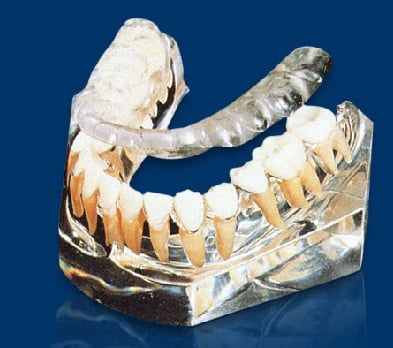

The Temporomandibular Joint (TMJ) connects the lower jaw to the temporal bone on the side of the head. You can feel it by placing your fingers just in front of your ears while opening and closing your mouth. These flexible joints allow smooth movement for chewing, speaking, and yawning. When the TMJ isn’t functioning correctly, it can lead to TMD—a cycle of pain, muscle spasms, and jaw problems that can severely impact your daily life. At Tomlinson Dental, our Tampa team offers personalized treatment plans to correct TMJ dysfunction and relieve symptoms. TMD encompasses a range of conditions stemming from an unbalanced or uncomfortable TMJ, often presenting as pain in the jaw, muscles, and surrounding areas. When teeth are missing, misaligned, or crowded, chewing and biting become unbalanced, causing the TMJ and associated muscles to work harder, leading to painful symptoms. Tomlinson Dental in Tampa provides comprehensive assessments and treatments for TMD, helping patients regain comfort and functionality. TMD can be categorized into three main types:

- Myofascial Pain – The most common form of TMD, characterized by discomfort or pain in the muscles that control jaw movement, as well as in the neck and shoulders.

- Internal Derangement of the Joint – This refers to issues such as a displaced disc or injury to the condyle (the rounded part at the end of the jaw bone).

- Degenerative Joint Disease – Conditions like osteoarthritis or rheumatoid arthritis that affect the jaw joint.

Phase I :

Generally speaking, it includes the fabrication of an orthotic. An orthotic is an acrylic device that is worn on the lower teeth 24 hours a day. The orthotic is designed to reposition the jaw to the correct neuromuscular position.

First we analyze the bite, decide which muscles are causing the pain, and where the current position of the bone is and the disc. All this is done with the aid of advanced equipment like the TENS unit, K7 jaw tracking, Sonography, EMG's and advanced x-rays like Tomography, CT Scans and MRI's of the TMJ.

This will help us determine the best and most comfortable position of the TMJ and the muscles. Once that position is determined, we place the orthotic on the lower teeth to keep the TMJ in that position.

Orthotics usually are worn for 4-6 months or until most of the symptoms are relieved. Once an orthotic is in use, the symptoms start gradually disappearing until we reach a point that both the doctor and the patient are satisfied with. This concludes Phase I of the treatment.

- Replace missing teeth.

- Restore all the lower and/or upper teeth with crowns and veneers to preserve the optimal occlusion (bite) that was achieved with the orthotic in phase I.

Denture patients with TMJ/TMD:

Many patients complain that when they received dentures, they noticed pain in the jaw, headaches, ear problems and other symptoms. Sometimes taking the dentures out will relieve those symptoms.

If your dentures are not made to the correct bite, or vertical dimension, it will most likely cause these symptoms. Simple adjustments could get rid of these symptoms, but sometimes a whole new set of dentures need to be made according to the neuromuscular principles, to get rid of your headaches or jaw pain.